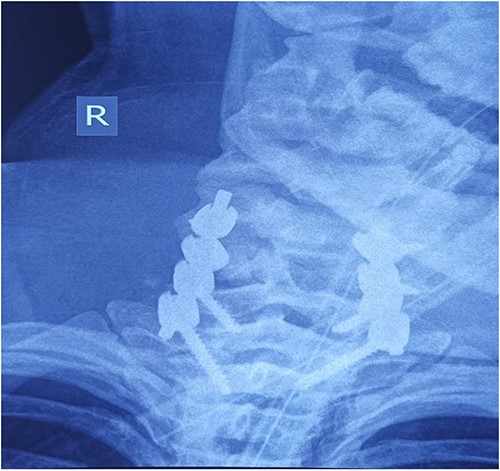

Computed tomography revealed complete traumatic dislocation of C6/C7 with consequent transection of the spinal cord (Figs 1 and 2).

Computed tomography finding (3D reconstruction): C6/C7 dislocation.